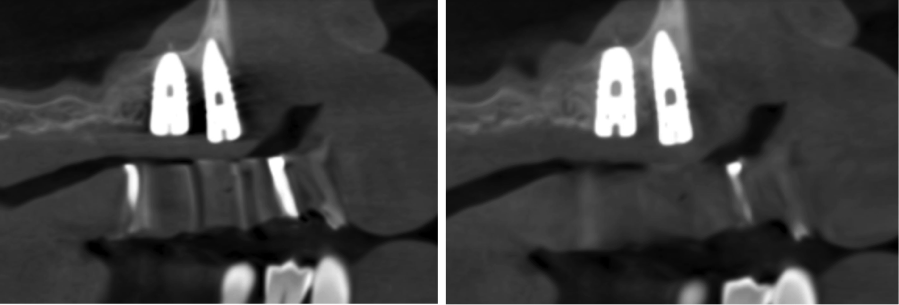

(4.) When compared to the original CBCT image (left), the application of artifact reduc- tion algorithms have improved the visualization between the two dental implants (right image).

Figure 4